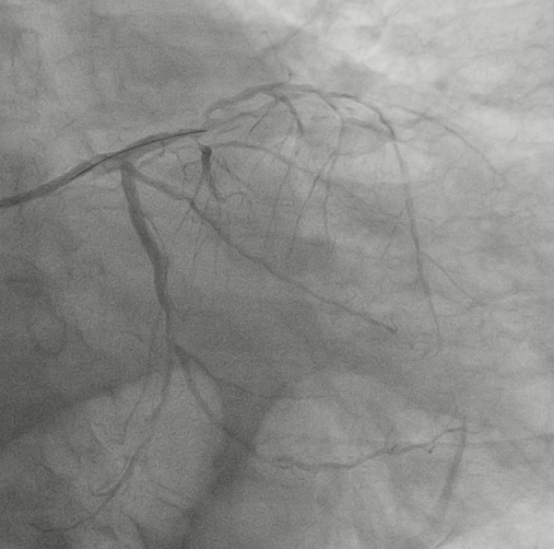

呼吸机、除颤仪、心脏辅助装置IABP等也都处于备用状态,术者和护士有条不紊、紧张高效,手术开始后在回旋支近段快速植入1枚支架,左主干扩张完也顺利植入1枚支架,至此,心脏血流明显改善,患者逐渐平静下来,呼吸也没那么急了。

李主任在台上问患者还能否耐受手术,可以的话,争取半小时内尝试开通前降支慢性闭塞病变,患者感觉气促好多了,说“还能再躺一会儿”,在患者的积极配合下,李主任应用双导丝技术很快通过慢性闭塞段,充分扩张病变段后予药物球囊处理。

在1小时内,左主干病变解决了,前降支的慢闭和回旋支的重度狭窄也一并处理了,手术达到了预期最好的效果。

图4:左冠术前回旋支重度狭窄

图5:左冠术后回旋支

图6:左主干和回旋支重度狭窄、前降支慢性闭塞

图7:左冠术后:左主干狭窄解除、前降支开通